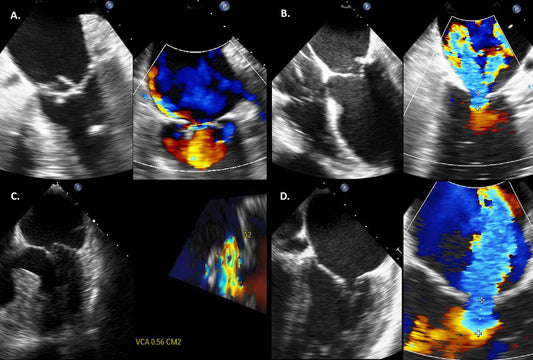

二尖瓣关闭不全和二尖瓣狭窄有什么区别?

总之,虽然二尖瓣反流和二尖瓣狭窄都会影响二尖瓣,但它们在原因、症状和治疗选择方面存在明显差异。如果您怀疑自己可能出现与任一病症相关的症状,请务必咨询医疗保健专业人员以获得准确的诊断和适当的治疗计划。